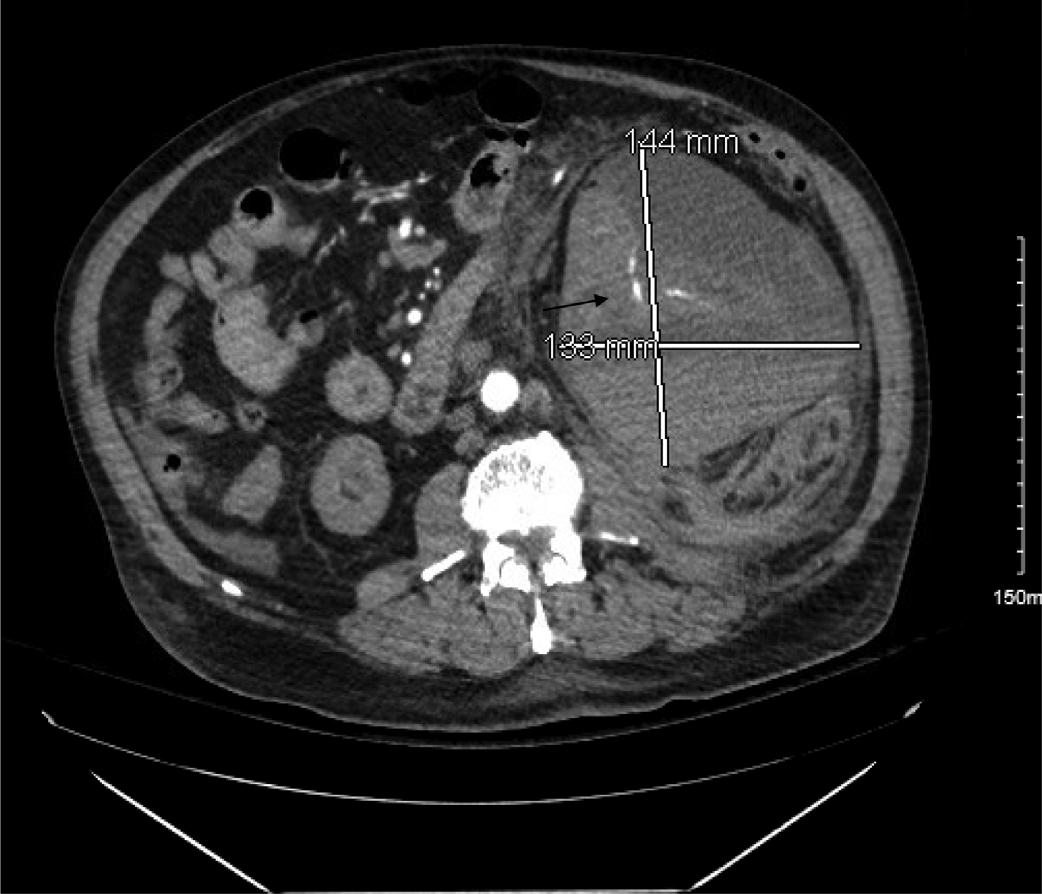

Emergentcomputedtomographyoftheabdomenand pelvisrevealedalargeleftretroperitonealandperitoneal hematomasecondarytoleftRAArupture,aswellasconcern fordevelopingsplenicinfarctsintheleftlowerrenalpole (Image).Thepatientwastakenemergentlytotheoperating room(OR)forexploratorylaparotomywithintwohoursof EDarrival.Sheunderwentsuprarenalcross-clampingwith repairoftheleftrenalarteryandligationofrenalvessels.She returnedtotheORtwodayslaterforleftnephrectomyand abdominalclosure.Shewasextubatedandtransferredtothe floor.Shewasdischargedhometwodayslaterin goodcondition.